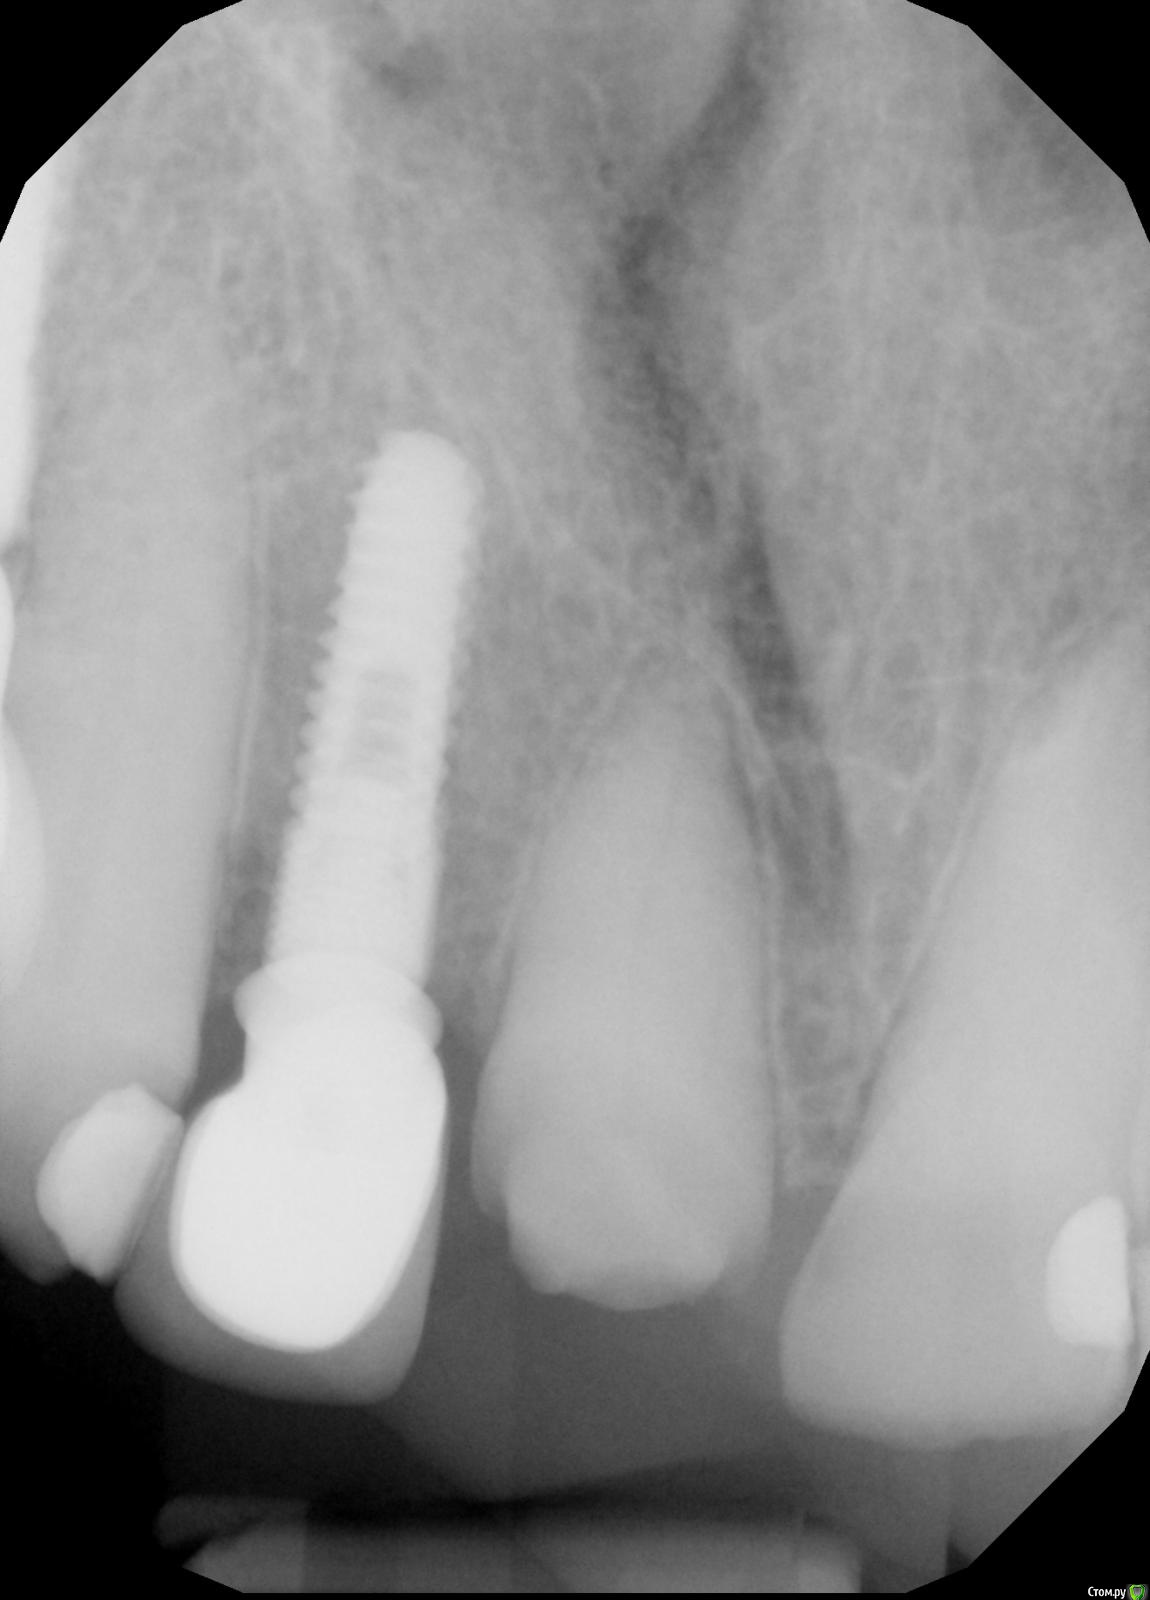

adent Опубликовано 20 июня, 2020 Поделиться Опубликовано 20 июня, 2020 Здравствуйте! Спала коронка с зуба номер 8.Он обточен и остаток зуба имеет размер примерно 2 мм на 2 мм.Посоветуйте пожалуйста.Может можно (целесообразжно) поставить штифт в остаток зуба чтобыновая коронка держалась надежнее? Спасибо! АнатолийP.S. Снимок прикреплен Ссылка на комментарий

adent Опубликовано 20 июня, 2020 Автор Поделиться Опубликовано 20 июня, 2020 Снимок переднего зуба номер 8 прикреплен здесь.Прошу прощения по неопытности не получилось прикрепить файл в первом сообщении. Ссылка на комментарий